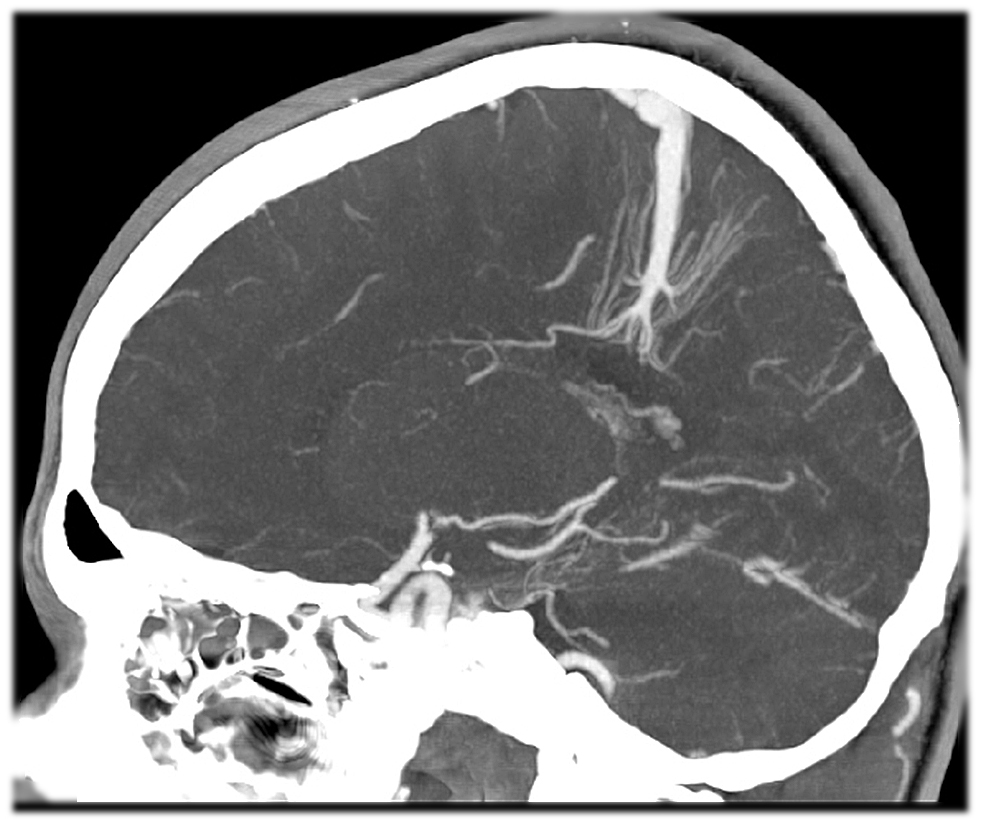

Мр картина венозной ангиомы левой гемисферы мозжечка - 96 фото